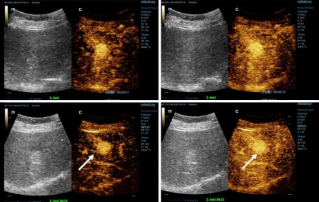

![Nauwkeurigere diagnoses met HiFR CEUS]() Nauwkeurigere diagnoses met HiFR CEUSContrastverrijkte echografie (CEUS: Contrast-enhanced ultrasound) is een zeer dynamisch vakgebied en in de afgelopen jaren is de beeldkwaliteit dankzij technologische innovaties verder verbeterd. Een van deze innovaties is contrastverrijkte echografie met hoge framesnelheid (HiFR CEUS: high frame-rate contrast-enhanced ultrasound). Hiermee worden in dezelfde tijd tot tien keer zo veel beelden gegenereerd dan met conventionele echografie.Echografie | Algemene beeldvorming 2022-12-16

Nauwkeurigere diagnoses met HiFR CEUSContrastverrijkte echografie (CEUS: Contrast-enhanced ultrasound) is een zeer dynamisch vakgebied en in de afgelopen jaren is de beeldkwaliteit dankzij technologische innovaties verder verbeterd. Een van deze innovaties is contrastverrijkte echografie met hoge framesnelheid (HiFR CEUS: high frame-rate contrast-enhanced ultrasound). Hiermee worden in dezelfde tijd tot tien keer zo veel beelden gegenereerd dan met conventionele echografie.Echografie | Algemene beeldvorming 2022-12-16 -